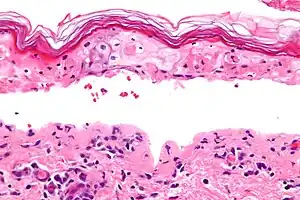

| Micrograph of confluent epidermal necrosis. H&E stain. | |

Erythema multiforme major is a form of rash with skin loss or epidermal detachment.

The term "erythema multiforme majus" is sometimes used to imply a bullous (blistering) presentation.[2]

In this view, EM major, SJS and TEN are considered a single condition, distinguished by degree of epidermal detachment.[3][4]